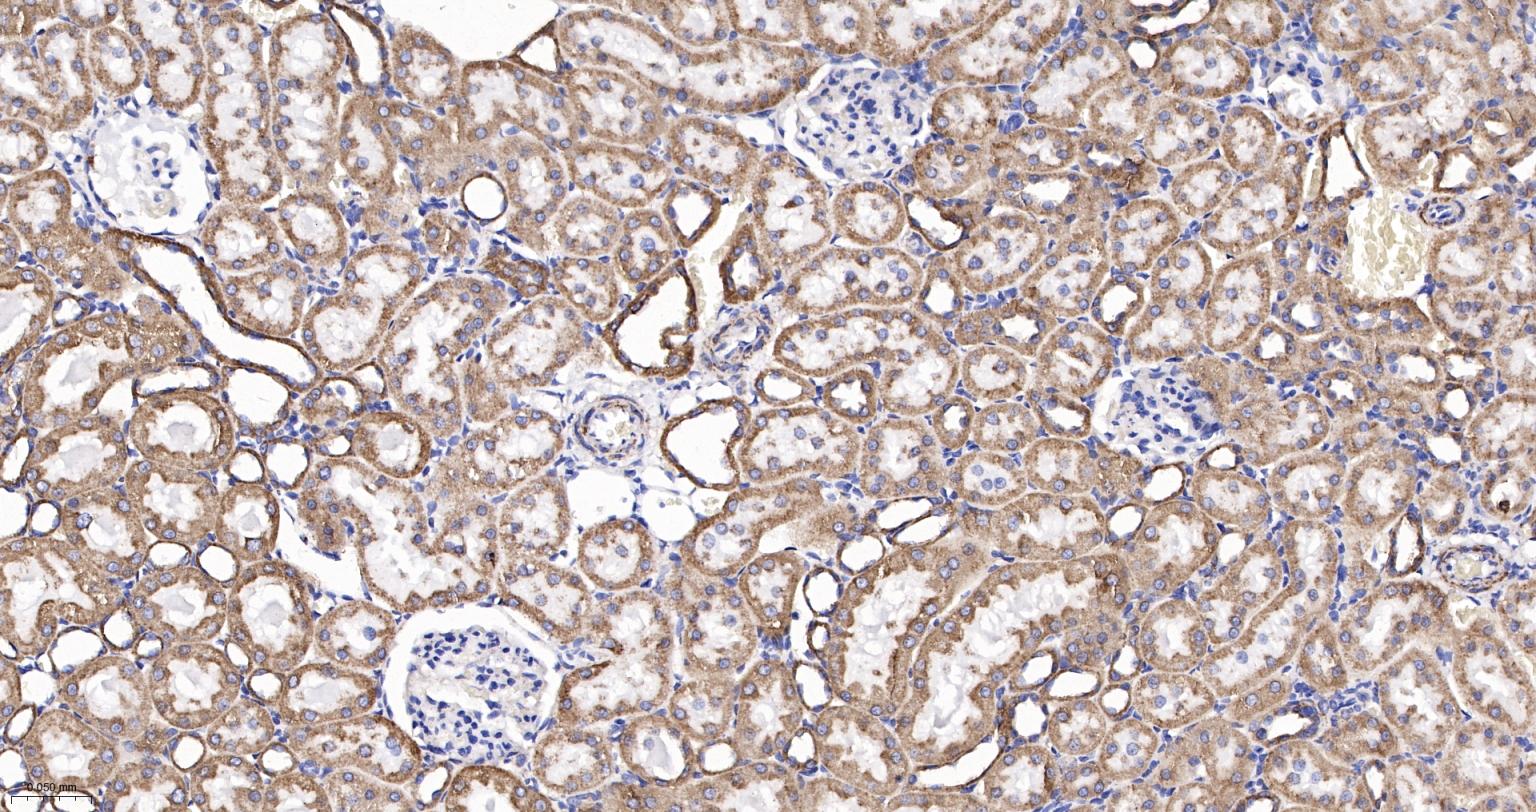

Paraformaldehyde-fixed, paraffin embedded Human Kidney; Antigen retrieval by boiling in sodium citrate buffer (pH6.0) for 15 min; Antibody incubation with Cytochrome C Monoclonal Antibody, Unconjugated(bsm-52050R) at 1:200 overnight at 4°C, followed by conjugation to the SP Kit (Rabbit, SP-0023) and DAB (C-0010) staining.